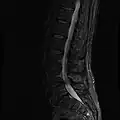

MRI

MRI lumbar spine with degeneration (sagittal T2 FRFSE)

MRI lumbar spine with degeneration (sagittal T1 FSE)

MRI lumbar spine with degeneration (sagittal FAST STIR)- MRI lumbar spine pre-hemilaminectomy (sagittal T2 FRFSE)